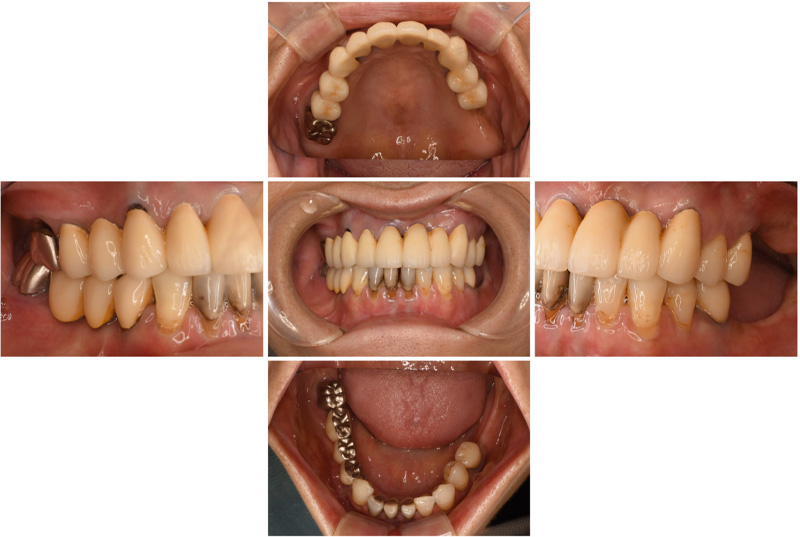

57歳男性

治療後